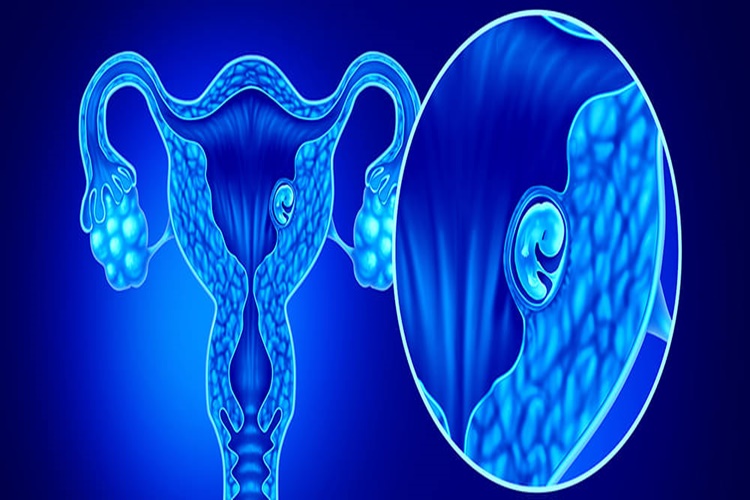

Kürtaj Kaçıncı Haftada Yapılır?

Kürtaj, gebeliğin hangi haftasında yapılacağına bağlı olarak değişir. Genellikle kürtaj, hamileliğin ilk 10 ila 12 haftası içinde yapılır. Ancak, bazı durumlarda tıbbi veya yasal nedenlerle daha ileri bir tarihte de yapılabilir. Hamilelik haftası ne kadar ileri olduğunda, kürtaj işlemi o kadar karmaşık hale gelebilir ve riskler artabilir. Bu nedenle, kürtaj gereksinimi olduğunda mümkün olan en kısa sürede bir sağlık uzmanına başvurmak önemlidir.

Gebelikte Alttan Muayene Kaçıncı Haftada Yapılır?

Gebelikte alttan muayene, genellikle gebeliğin erken dönemlerinde rutin prenatal bakımın bir parçası olarak yapılır. İlk alttan muayene genellikle gebeliğin ilk trimesterinde, yani yaklaşık 8 ila 12 hafta arasında yapılır. Ancak, her gebelik farklıdır ve bazı durumlarda muayene daha erken veya daha geç bir zamanda yapılabilir. Alt muayene, gebelik boyunca düzenli aralıklarla devam eder ve gebelik süresince anne ve bebeğin sağlığını izlemek için önemlidir.